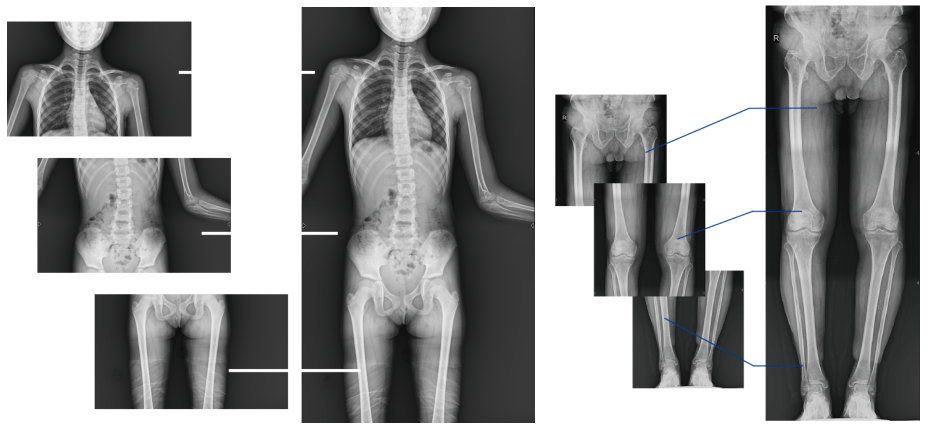

对于脊柱畸形及下肢畸形严重的患者,一般需要进行手术校正治疗,在诊治时往往需要以DR检查为主要依据,来对病变部位进行测量。常规DR不能一次性完成全脊柱或全下肢X光影像拍摄,需分别拍摄颈椎、胸椎、腰椎、骶尾椎的X光片,只能观察到局部的侧弯情况,看不到三者之间的连续性,增加了疾病诊治难度。

普利德多功能动态DR

动态DR全景拼接功能突破平板尺寸长度限制,可进行立卧位摄影,对脊柱、下肢及下肢静脉造影进行分段摄片,然后对分段图像进行拼接,在一幅X光图像上完整显示全脊柱或下肢整体形态,获得全脊柱或全下肢图像,有效解决了传统X光片不能一次成像问题,通过直观显示脊柱和下肢的整体解剖形态及侧凸部位,为临床治疗提供重要参考依据。

全脊柱成像对于脊柱侧弯的诊断治疗、手术方案的制定具有重要的参考价值;全下肢成像对于髋关节、膝关节角度的测量、髋和膝关节矫形手术、人工关节置换术等具有重要的参考价值,同时在创伤外科、康复科患者的检查、诊断和治疗中也发挥着重要的作用。

行全脊柱全下肢影像拼接时,影像密度均匀、清晰、接缘处过渡自然,图像质量高,完全能满足临床观察、诊断及测量要求。并且,拍片过程更加操作便捷,拍摄时间短,检查效率高,能使患者得到快速诊断,及时治疗,为临床医生和患者带来更大的便利,大大助力医院医疗服务能力的提升!